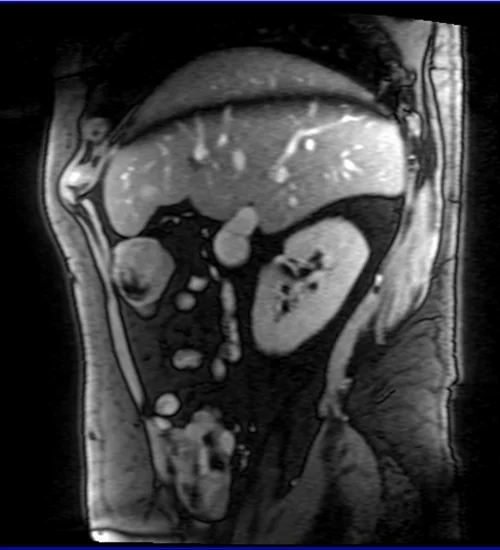

ABDOMEN CORONAL